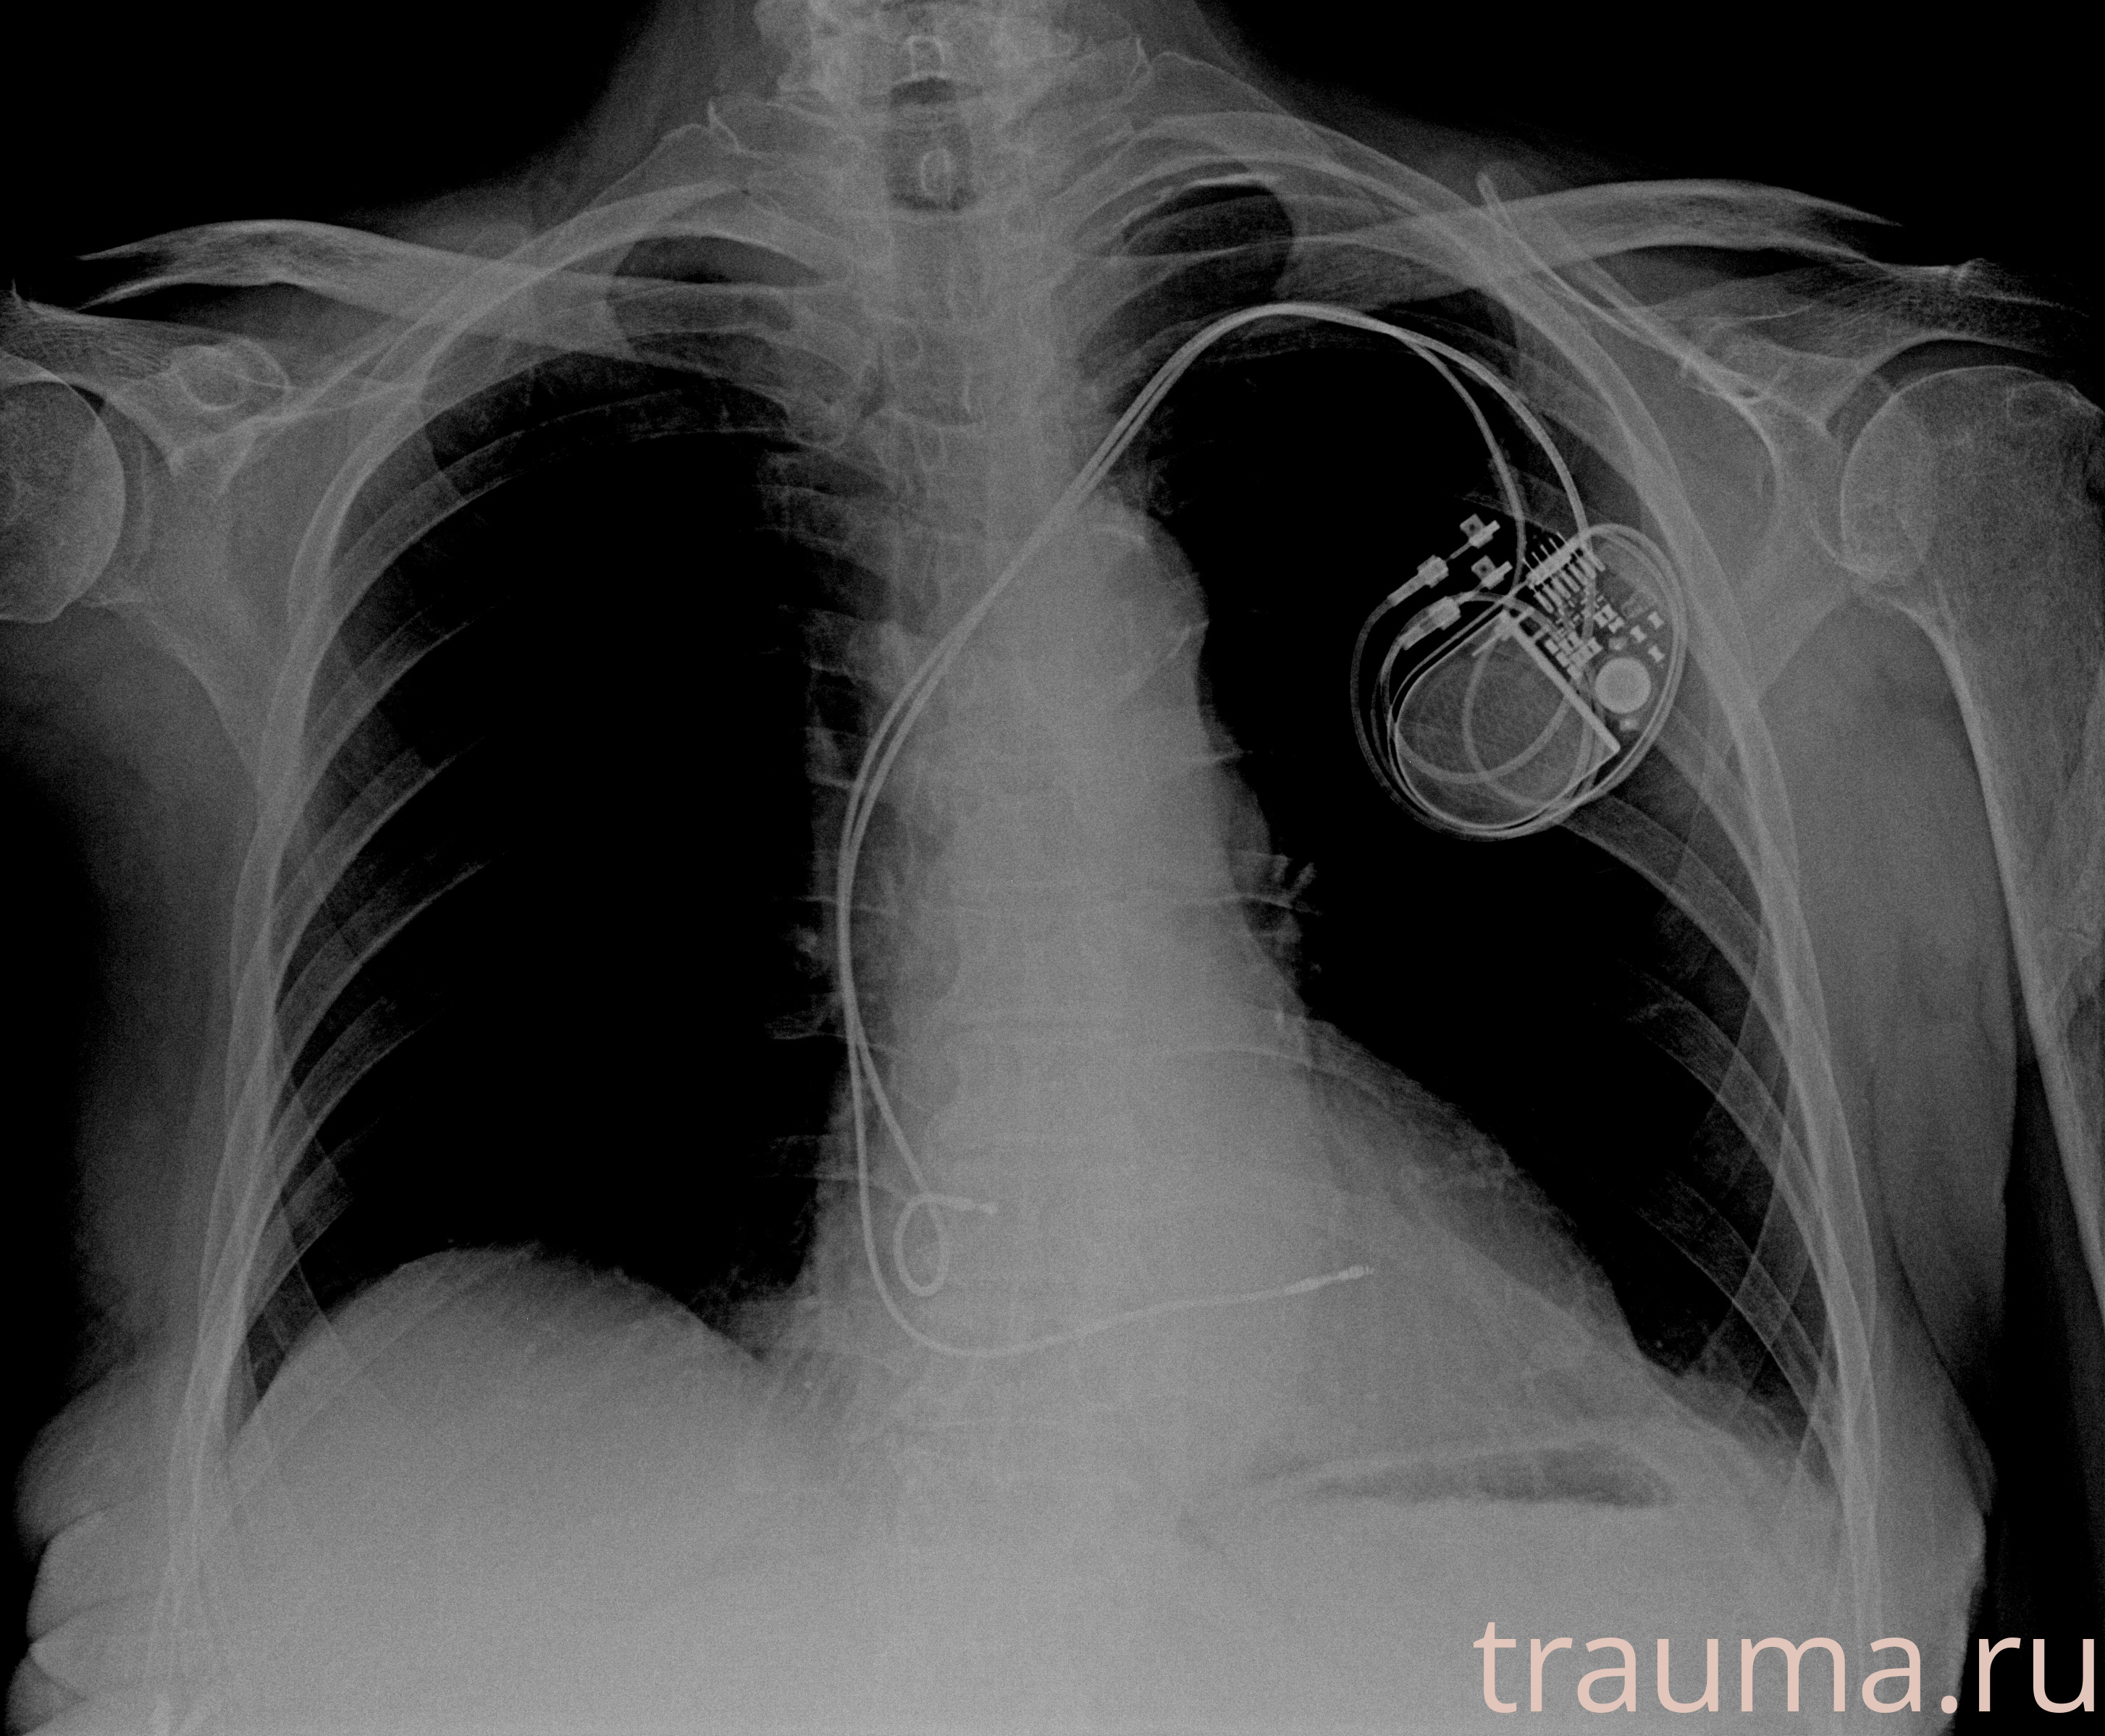

Рентгенограммы